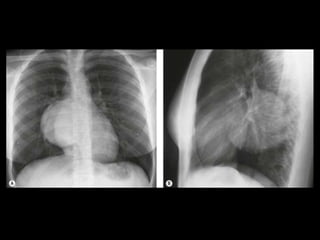

Sequestro pulmonar

Definição: segmento de tecido pulmonar que é

separado da árvore brônquica e recebe seu

suprimento sanguíneo de uma artéria sistêmica;

Dois tipos: intralobar e extralobar;

A maioria dos sequestros são tipo intralobar;

O suprimento vascular em 80-90% dos casos

provêm da artéria aorta descendente;

Complicações: hemoptise e BCP repetição;

Diagnóstico: identificação do vaso anômalo.

Sequestro intralobar com infecções recorrentes